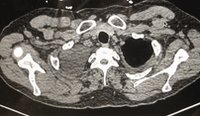

ICU stories: Middle-aged pt w/o significant PMHx presented to the ED on a Friday afternoon w SOB/cough x 2 wks. Vaxed x2 but tested C19(+). BP 120/90, Sat 98% on 2 l/m. ECG: new-onset Afib/HR 140/QTc 500. CXR attached; read as RLL infiltrate. Labs: Na 125, BNP 800 (nl<100),

☝️Full IVC and large R effusion. The admission CXR was read as "no evidence of pleural effusion". This was the chest CT for comparison: